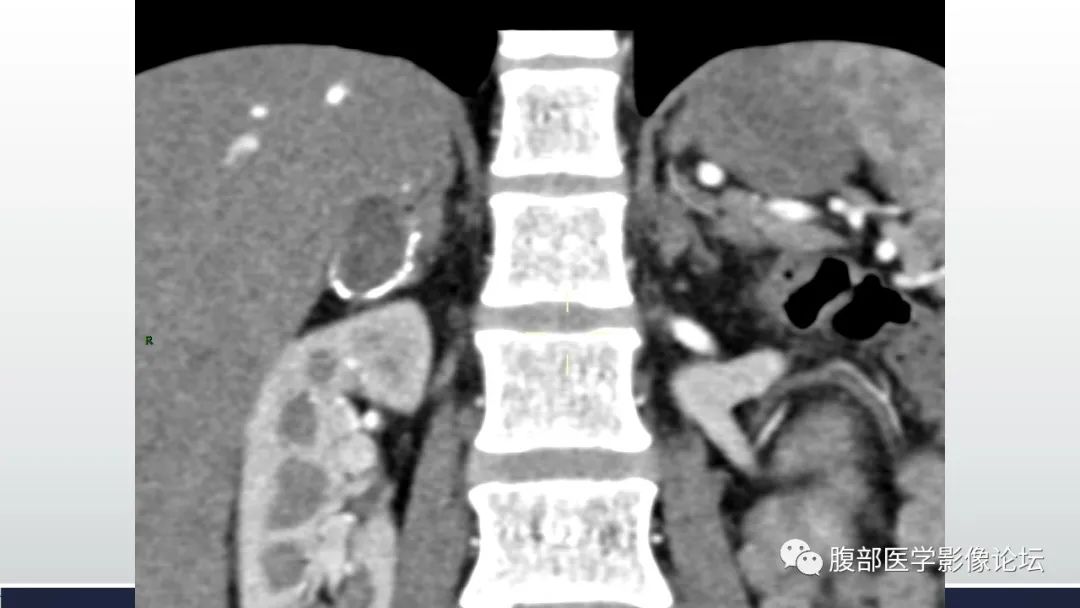

肾上腺平滑肌瘤伴钙化1例CT影像

李广明:右侧肾上腺外侧支结节,环状钙化,其内以囊性为主,尚可见稍高密度灶,增强强化不明显,左侧肾上腺稍增生。考虑1囊肿类,病灶环状钙化,需要优先考虑囊肿病变出血所致,a血肿机化及囊变,一般有外伤病史。b支气管囊肿,影像表现亦符合。2炎症,结核,肾上腺结核一般伴有爱迪生氏综合症,该患者临床没有提示。3肿瘤神经源性,强化偏弱,此种改变不典型。综合考虑肾上腺良性病变,囊肿类首先考虑,陈旧性血肿或支气管囊肿。建议核磁检查,除外肿瘤囊变。 医学百科网 | YxBaike.Com

结果:肾上腺平滑肌瘤 肾上腺平滑肌瘤一般无明显临床症状,多在体检或其他疾病临床诊治中偶然发现,亦呈“偶发瘤”。但是个别患者因肿瘤增大对周围组织压迫而出现腰部疼痛等症状。由于无内分泌功能,因此肾上腺皮髓质分泌功能正常,皮质醇、肾素、血管紧张素、醛固酮均无异常改变。影像表现为肾上腺区圆形或类圆形实质性肿块,质地均匀,部分有钙化,强化不明显,确诊有待病理检查。手术切除为主要治疗方法,术后无复发。 医学百科网 | YxBaike.Com

珠联璧合:定位:右侧肾上腺外支。

定量:环形钙化,中心密度减低为主,见少许密度稍高区,增强扫描未见强化;中年女性,平素健康。

定性:良性。

定病:结核>血肿机化>神经源性肿瘤。 医学百科网 | YxBaike.Com

邱勇刚:右肾上腺囊性占位,病灶有一定张力,囊内密度偏高,边缘环形钙化,内部轻度强化,考虑良性病变。疾病谱肾上腺血肿,囊肿,完全囊变的神经鞘瘤,节瘤。本例有张力不符合节瘤,强化不太符合神经鞘瘤。血管瘤太少见,考虑血肿>血管瘤。

医风听雨:右侧肾上腺蛋壳样钙化病灶,内部密度不均,(40到60多),这种表现很少见,分析只能一一排除,肿瘤(包括原发和转移),炎症,囊肿。肿瘤的话考虑良性肿瘤,炎症没有特别适合的病变,囊肿可以边缘钙化,但是这个病灶钙化比较厚,不符合。总结还是考虑良性肿瘤。 医学百科网 | YxBaike.Com